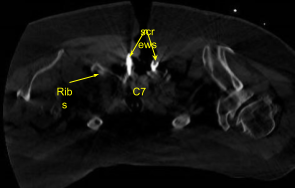

Airo CT scan was performed. Skin was sterilized with a DuraPrep solution. Sterile drapes were placed in the usual manner. A spinal needle was brought to the field and localized. 1% lidocaine with epinephrine was infused.

Self-retaining retractors were placed. Hemostasis was obtained with bone wax, Bovie and bipolar cautery. Neuronavigation array was affixed to the spinous process, clamped to the T1 spinous process. The patient was draped. CT scan was obtained, and data transferred to the neuronavigation computer, and accuracy verified.

Image-guided stereotactic frame with neuronavigation techniques were used to place the instrumentation. We placed bilateral T1 pedicle screws and decorticated with electric high-speed drill cannulating with the navigated pedicle finder, palpating for breaches, measuring the depths, under tapping by 11 mm and placing 30 mm x 5.0 mm titanium pedicle screws bilaterally without difficulty.